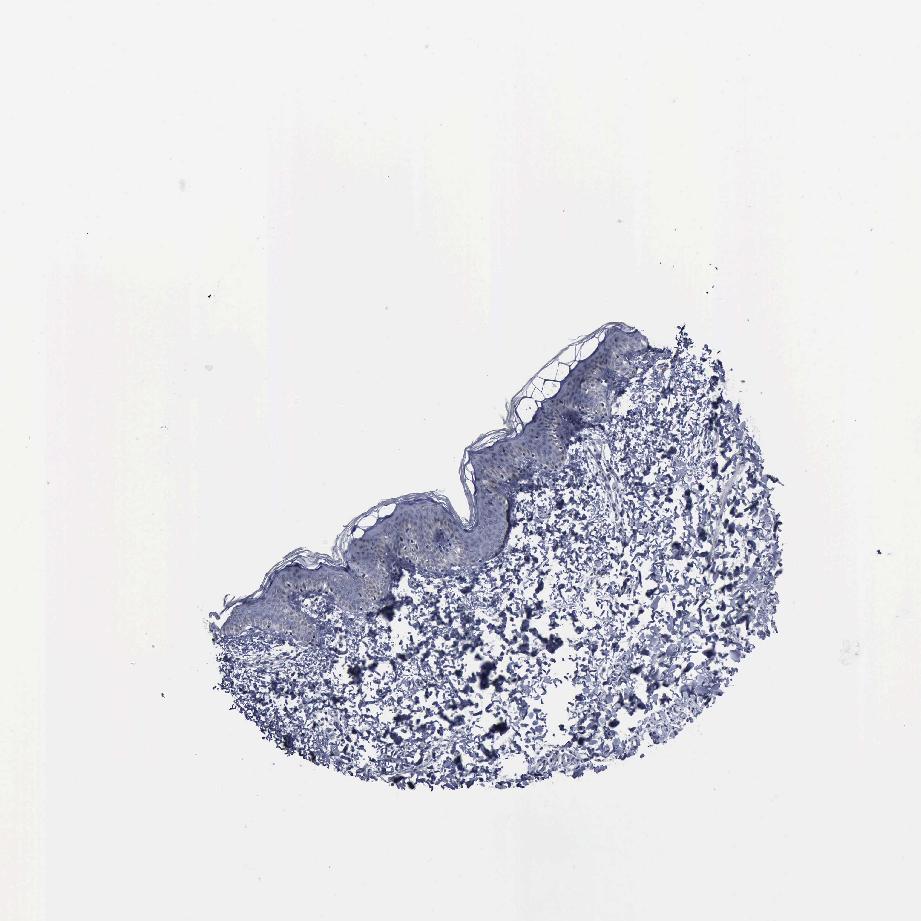

SKIN 1 - Antibody stainingi

Antibody staining in the annotated cell types in the current human tissue is reported as not detected, low, medium, or high, based on conventional immunohistochemistry profiling in selected tissues. This score is based on the combination of the staining intensity and fraction of stained cells.

Each image is clickable and will lead to virtual microscopy that enables deeper exploration of all samples and also displays staining intensity scores, fraction scores and subcellular localization as well as patient and tissue information for each sample.

Antibody HPA000807Antibody HPA001063

Langerhans MediumLow

Fibroblasts LowNot detected

Keratinocytes LowLow

Melanocytes MediumMedium